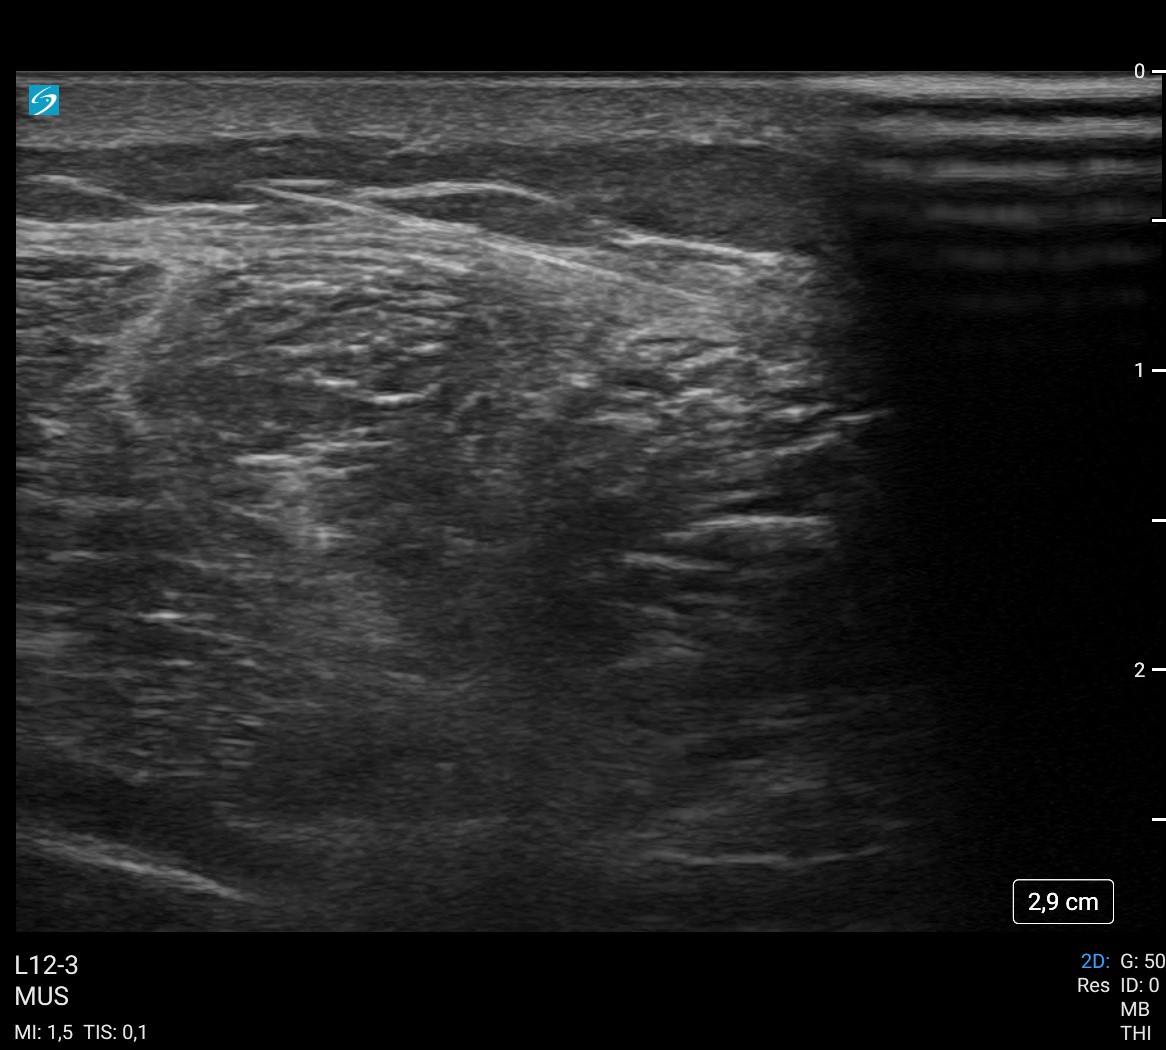

Con el punto de entrada y la imagen de la radiografía simple, como únicos datos para localizar la aguja, no teníamos la certeza de donde se encontraba. Nos servimos entonces de la ecografía para una localización exacta de la aguja, realizar la incisión y extraerla.Tratamiento y planes de actuación